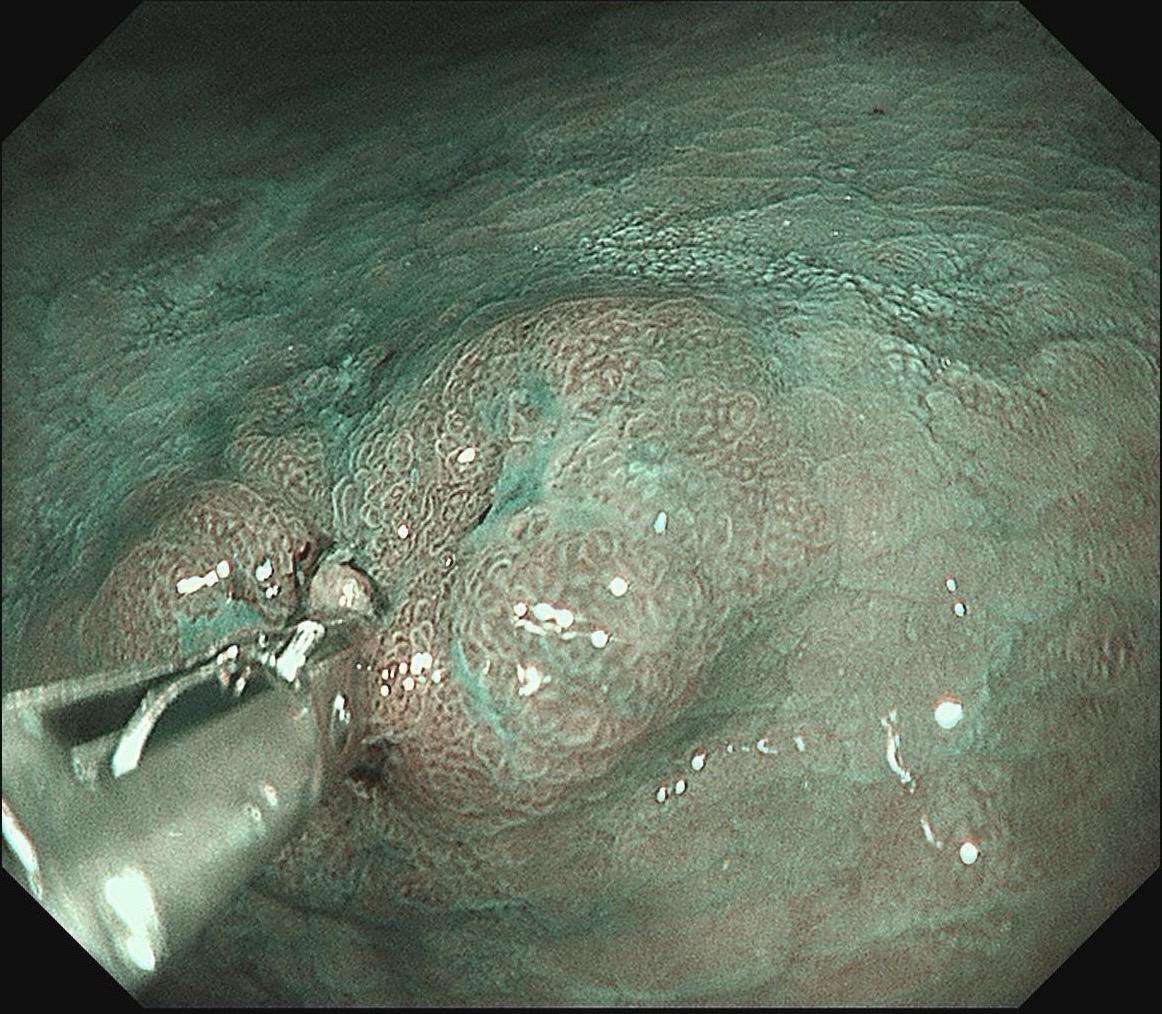

女,57岁,胃角。同事熟人,萎缩背景,色调淡黄,中央浅凹陷,腺管小而密集。